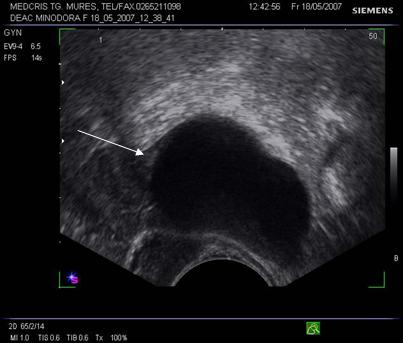

Fig. nr.391.

Endometriom ovarian vechi ,recidivat postoperator,

situat retrouterin

( sageata ). Se remarca ecogenitatea crescuta si asemanatoare ecostructurii endometriale uterine.